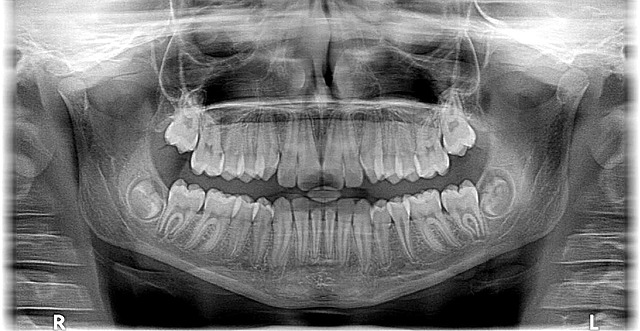

The practice’s state-of-the-art facility is designed with patient satisfaction in mind, featuring the latest technology to ensure precise diagnoses and effective treatments. From advanced X-ray machines to digital imaging, their equipment delivers unparalleled accuracy, enabling Dr. Cazares to create personalized treatment plans that address each patient’s unique orthodontic challenges. Whether it’s addressing mild misalignments or more complex bite issues, the team approaches every case with a blend of scientific expertise and compassionate care.

Our state-of-the-art facility is equipped with the latest technology, enabling us to provide precise diagnoses and effective treatments. For instance, our advanced 3D imaging allows for a detailed understanding of jaw structures and tooth positions, facilitating personalized treatment plans tailored to each patient’s unique needs. We offer various options, including traditional metal braces, clear aligner trays like Invisalign®, and innovative tools like Propel™ accelerated orthodontic treatment. These advancements not only enhance the effectiveness of care but also make the experience more comfortable and efficient for our patients.